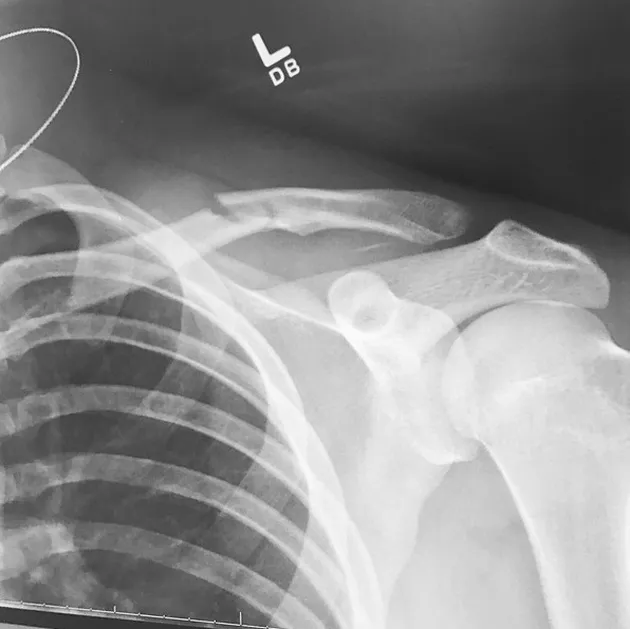

Asyik menuruni gunung dengan papan ski, Brooklyn pun mengalami kecelakaan. Ia terjatuh hingga mengalami patah tulang di bagian pundaknya.